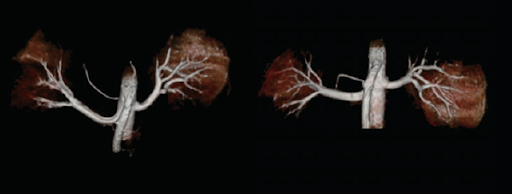

Усовершенствованные методы неконтрастной МР томографии снижают риски для некоторых групп пациентов. С томографом Vantage Titan можно проводить такие исследования, как FBI, FBI Navi , CIA, SPEED, FSBB, Time-SLIP.